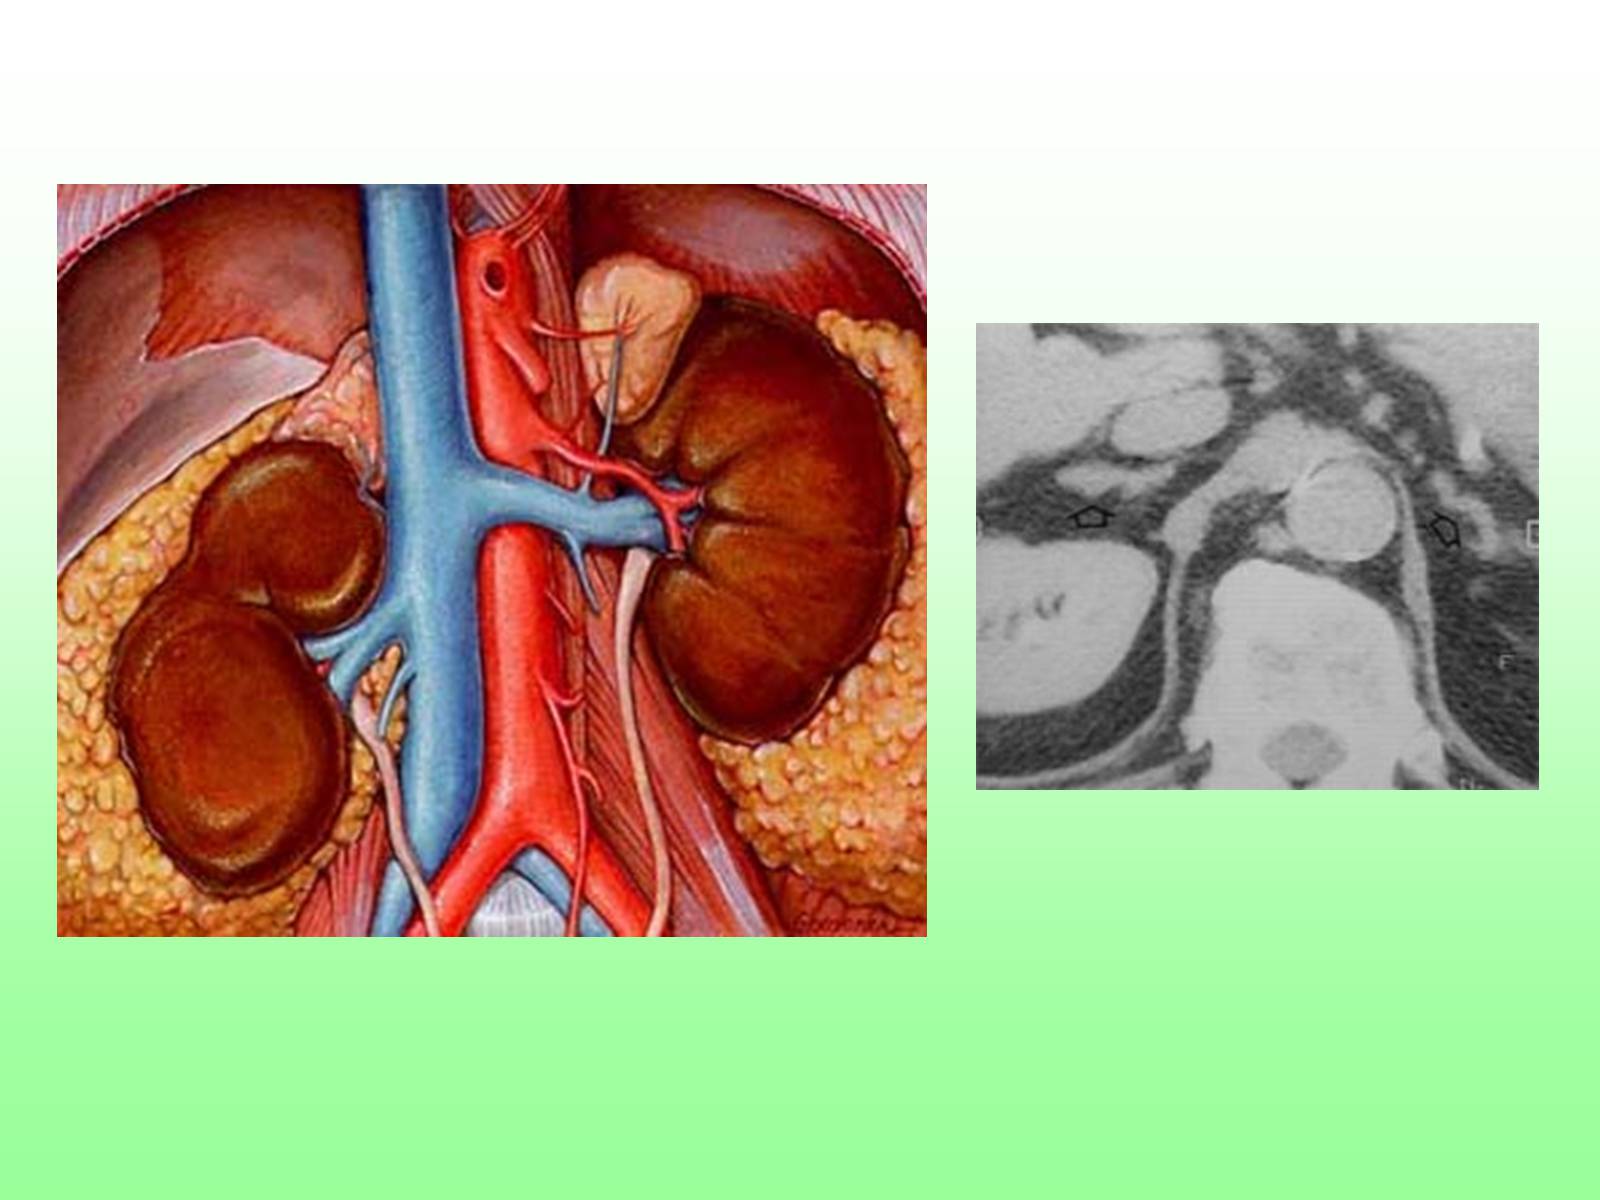

Надпо́чечники — парные эндокринные железы

позвоночных животных и человека.

Располагаются по центру человеческого тела, а именно рядом с верхним полюсом каждой почки.